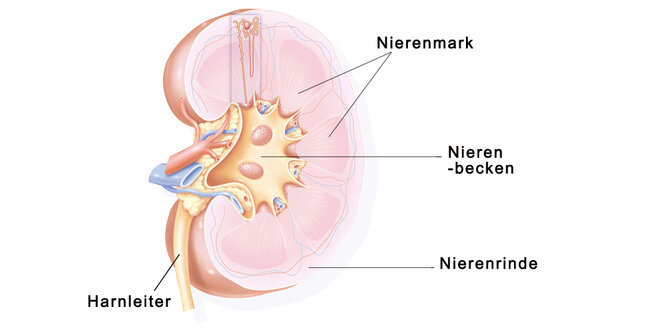

Bei der Glomerulonephritis handelt es sich um eine Entzündung der Nierenkörperchen (Glomeruli). Die Nierenkörperchen bestehen aus einer Art Gefäßknäuel in der Nierenrinde (siehe auch Hintergrundinformation weiter unten), in denen der sogenannte Primärharn gebildet wird. Unterteilt werden die Glomerulonephritiden in eine primäre oder sekundäre Glomerulonephritis. Handelt es sich um eine Entzündung der Nierenkörperchen, ohne weitere Systemerkrankung spricht man von einer primären Glomerulonephritis, ist die Entzündung dagegen Folge einer anderen Erkrankung außerhalb der Nieren, handelt es sich um eine sekundäre Glomerulonephritis.

Bei einer Nierenentzündung können aber auch die Harnkanälchen (Tubuli) und der sie umgebende Raum (Tubulointerstitium) entzündet sein, dann ist von einer tubulo-interstitiellen Nephritis die Rede. Als Folge davon treten Störungen in der Konzentrierung des Primärharnes auf.

Aufbau und Funktion der Niere